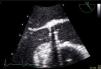

Case reportA 73-year-old female patient presented to the emergency department complaining of asthenia, weight loss (>10% of initial body weight) and fever (38–38.5°C) during the last four weeks. She had a history of a single-disc mechanical aortic valve implanted two years earlier due to severe aortic stenosis. She was taking warfarin and was doing well in the follow-up. After an initial diagnostic work-up, in which no infectious focus was identified, the patient underwent transthoracic and transesophageal echocardiograms. Both exams showed a normally functioning mechanical prosthesis, normal left ventricular systolic function, and no vegetations or images compatible with abscesses or other paravalvular complications (Figure 1).

One month later, the patient presented again in the emergency department complaining of abdominal pain and persistent asthenia and fatigue. An abdominal computed tomography scan showed a large splenic mass and an exploratory laparotomy was performed. Intraoperatively, an extensive abscess was noted which extended to the diaphragm and ipsilateral pleural cavity. The spleen was removed and the material collected for microbiological analysis. Given this setting, and to exclude potential embolic sources, echocardiographic assessment was repeated. The transesophageal echocardiogram showed multiple abscesses (Figure 2A, asterisk) surrounding the single-disc mechanical aortic prosthesis (Figure 2A, cross). There appeared to be no communication between the abscesses and the cardiac cavities, thus excluding the possibility of a pseudoaneurysm (Figure 2B, white arrow) and there were no signs of prosthetic dysfunction. The patient began appropriate antibiotic therapy and was referred for surgery.

Transesophageal echocardiogram in mid-esophageal short- (A) and long-axis (B) views of the aortic prosthesis, showing two abscesses (A, asterisk) surrounding the single-disc mechanical prosthetic valve (A, cross). There appears to be no rupture from these abscesses (B, white arrow) to the left ventricular outflow tract.